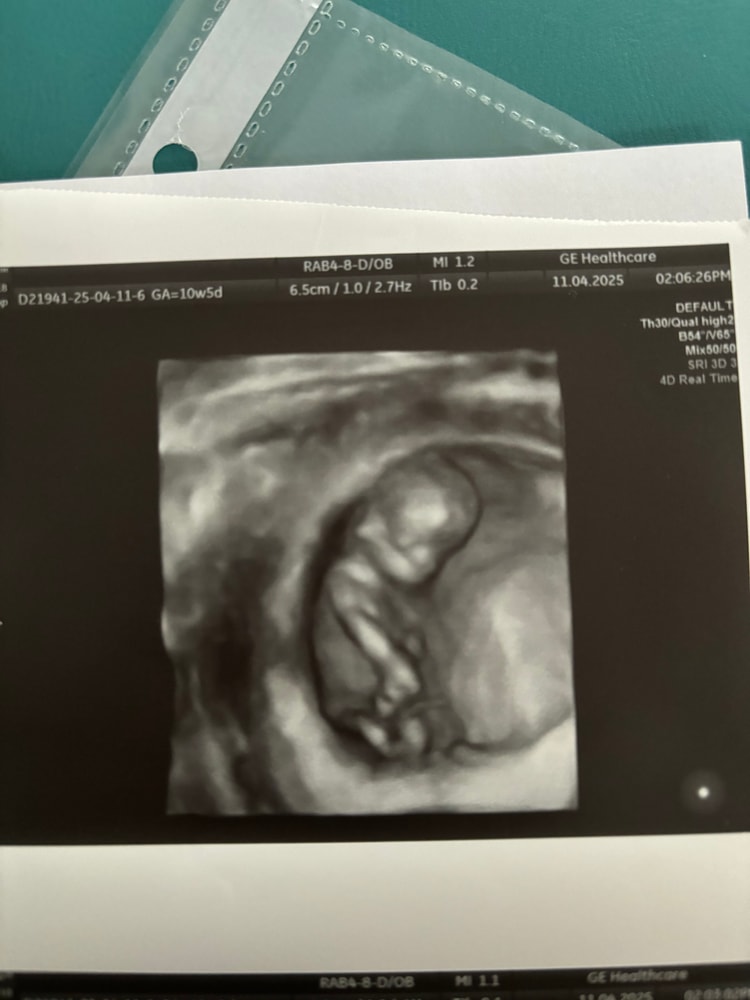

УЗИ 10.5 ❤️ Фото пупсика

УЗИ, КТГ, доплерРешила перед скринингом попасть еще раз на узи, малыш уже совсем человечек) по месячным срок 10.5, по УЗИ 11.1. Очень активный, машет ногами 😂 хотели глянуть пол,но ноги мешали,ну ничего)

Решила перед скринингом попасть еще раз на узи, малыш уже совсем человечек) по месячным срок 10.5, по УЗИ 11.1. Очень активный, машет ногами 😂 хотели глянуть пол,но ноги мешали,ну ничего)